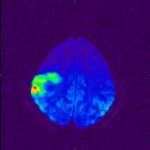

Meine MRT

Aufnahmen: |

MR-Angiographie (MRA) meiner Halsgefäße Stand: 03.03.2006 |